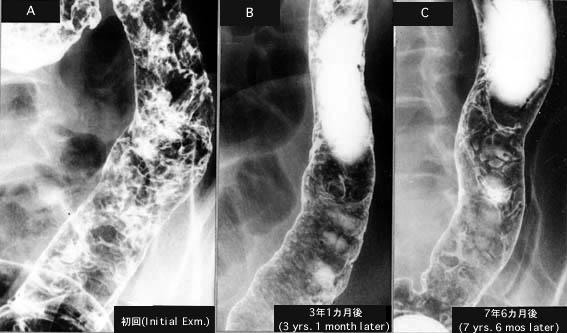

弥漫性的炎症性息肉病反复加重而又好转的溃疡性大肠炎

Tokyo Pref., 国立癌中心中央病院和九州癌中心共同完成

炎症性・溃疡性疾患/溃疡性大肠炎

大肠/降结肠

X线